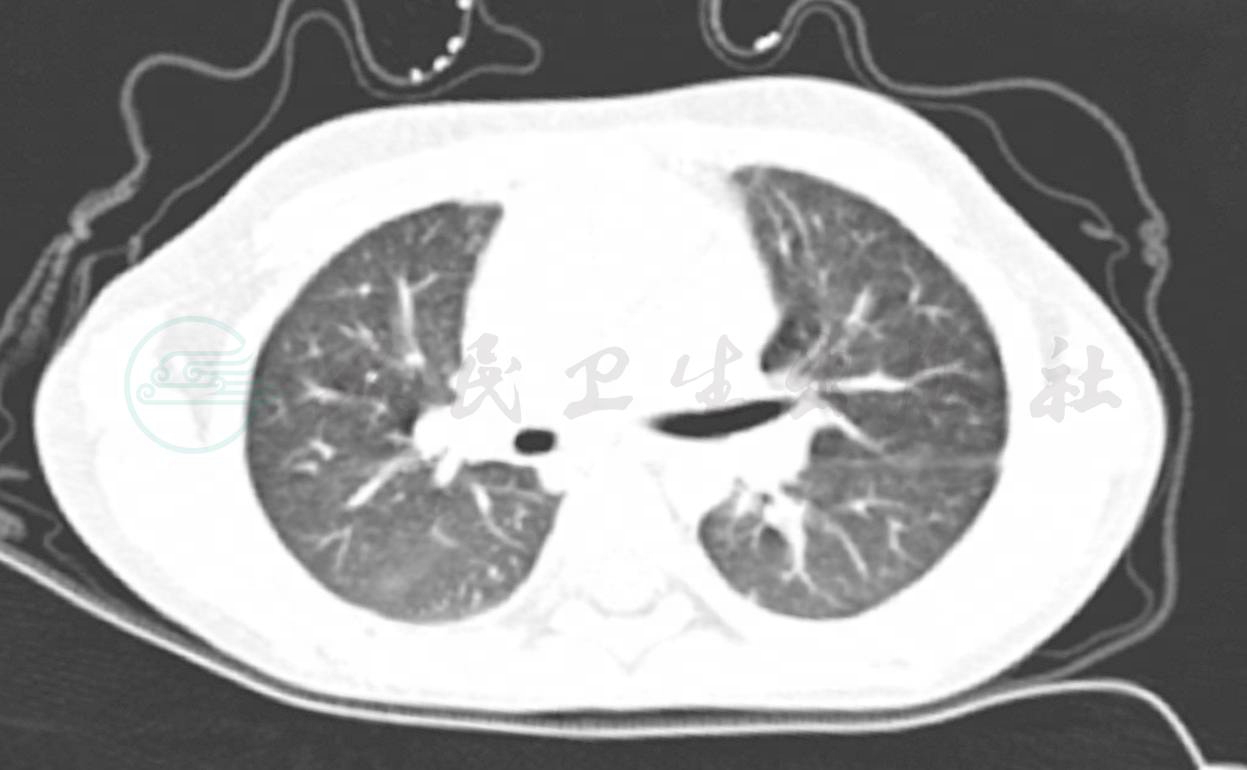

入院后因诊断尚不明确,根据病情分析完善相关检查,同时给予对症支持治疗,入院后当天完善肺部CT检查(图5),提示:①右侧胸腔少量积液;②肺纹理稍模糊,不除外小气道炎症。可见,患儿应用抗生素及少量激素后曾有过一过性缓解,但最终病情反复,且未找到病因,病情迁延不愈。

图5 入院后完善肺CT